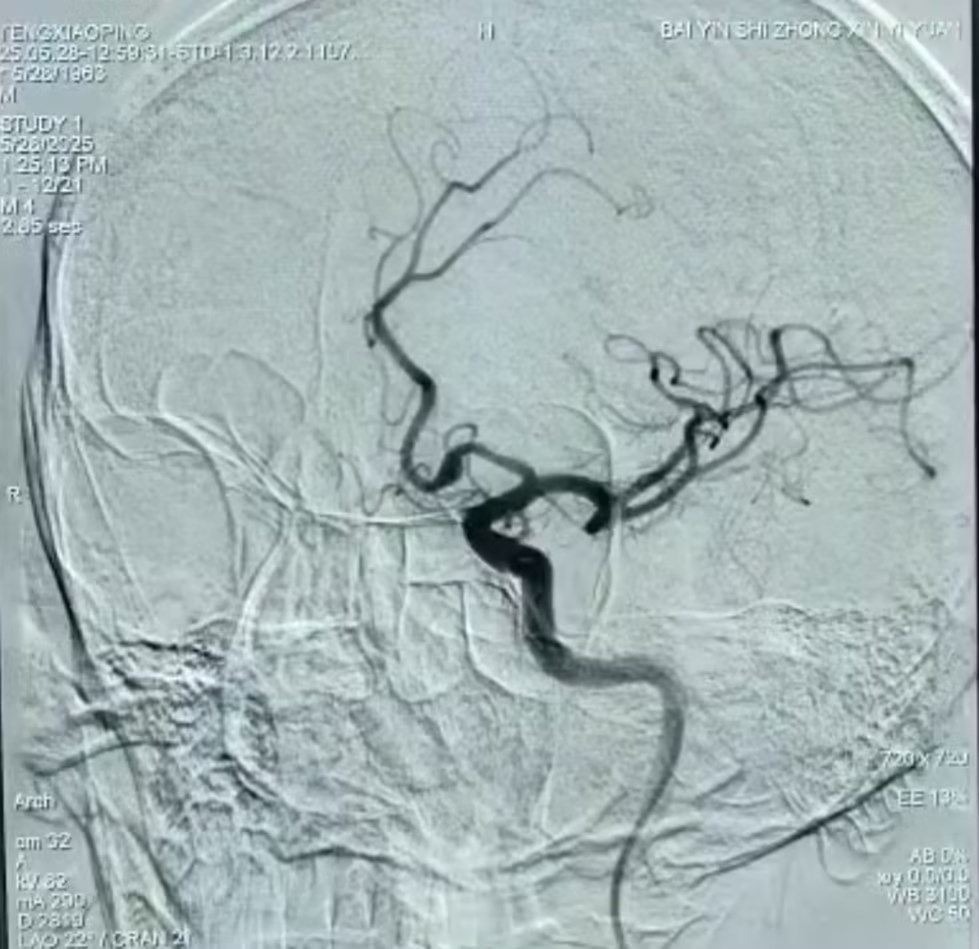

5月28日,神经内科团队应用血流导向密网支架,成功为一名大脑前A1段夹层动脉瘤患者实施微创介入手术,为一名62岁高危动脉瘤患者拆除“脑内炸弹”。这是医院首次采用血流导向密网支架治疗颅内动脉瘤,填补了医院在该技术领域的空白,标志着市中心医院神经介入治疗水平迈上了新台阶。 动脉瘤术前

手术过程中,医疗团队精准释放2.5mm×18mm血流导向密网支架,完全覆盖动脉瘤颈。术中即刻造影显示动脉瘤瘤腔内造影剂滞留,载瘤动脉及邻近血管通畅无狭窄,手术成功。